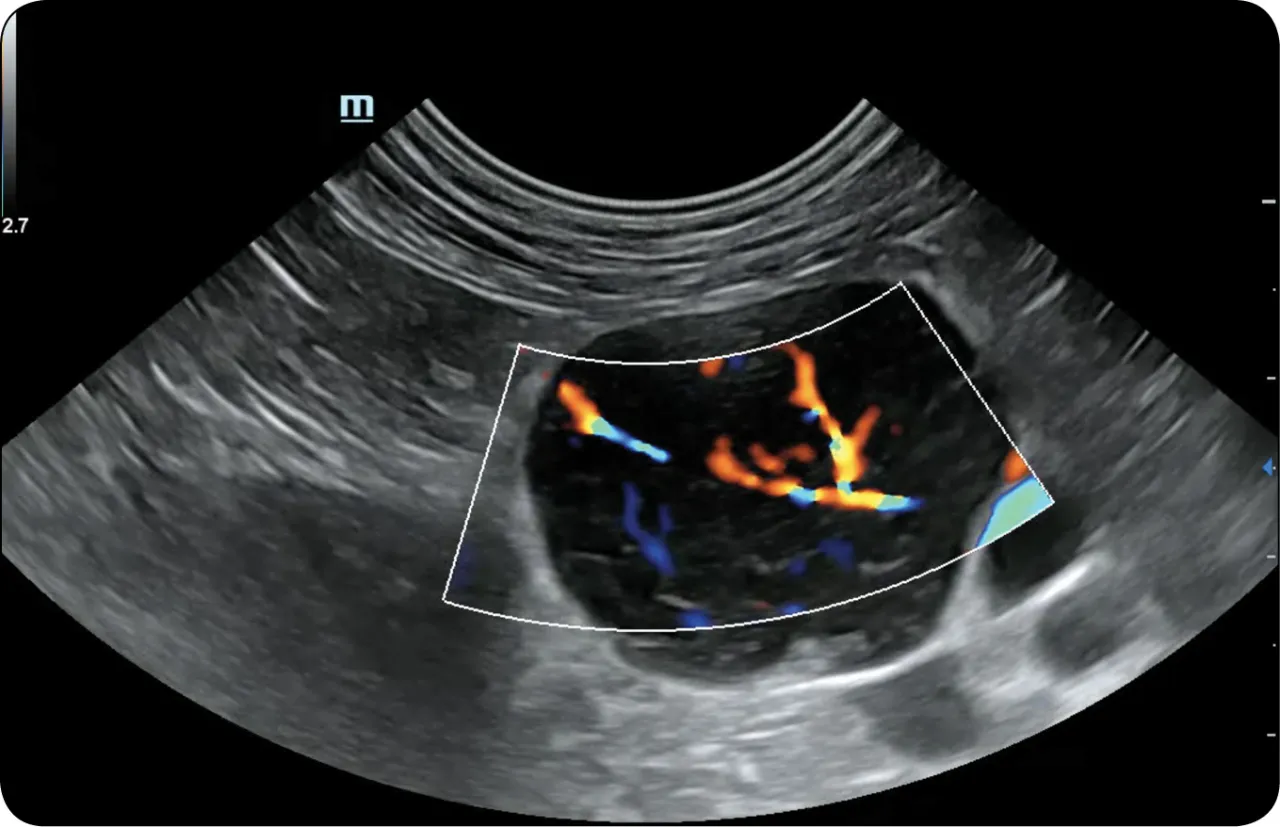

Krok trzeci: USG węzłów chłonnych jako kluczowe badanie obrazowe

Jeśli badania krwi nie dadzą jednoznacznej odpowiedzi lub lekarz uzna, że powiększone węzły chłonne wymagają dokładniejszej oceny, kolejnym krokiem będzie USG węzłów chłonnych. To nieinwazyjne i bezpieczne badanie obrazowe jest kluczowe. Pozwala ono ocenić wielkość, kształt, strukturę wewnętrzną węzła (np. obecność wnęki, która jest dobrym znakiem), a także jego unaczynienie. Na podstawie tych cech radiolog może wstępnie określić, czy węzeł ma charakter odczynowy (infekcyjny) czy też budzi podejrzenie procesu nowotworowego. W zależności od wskazań, w dalszej diagnostyce mogą być stosowane inne badania obrazowe, takie jak RTG klatki piersiowej, tomografia komputerowa (TK) lub rezonans magnetyczny (MR).Krok czwarty: kiedy konieczna jest biopsja i dlaczego jest "złotym standardem"?